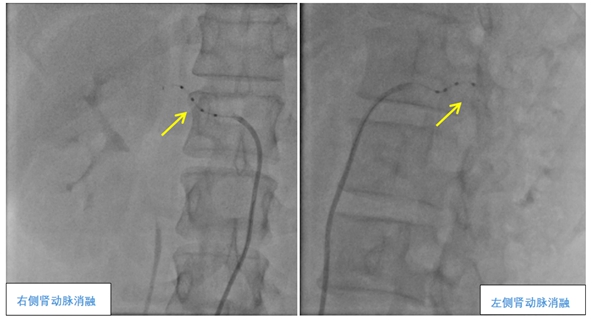

术中,夏文豪团队对患者双侧肾动脉主干及分支进行了全面、精准的消融,共消融了38个靶点,手术仅用1小时。术后,孔女士没有任何不良反应,第二天便能下床自由活动,第三天顺利出院。在之后的多次回访中,孔女士表示她的血压已经逐渐稳定,而且头晕头痛心悸等症状明显改善。

▲肾动脉去交感神经消融术(RDN)

夏文豪介绍,肾动脉去交感神经消融术是一种高血压微创介入手术,通过消融肾动脉周围的交感神经,降低其兴奋性,从而达到长效降压的效果。目前中山一医广西医院心血管内科团队在这一项全新领域中有着丰富的经验,已成功完成11例,指导桂林人民医院、桂林医学院第二附属医院、柳州工人医院、揭阳市人民医院等完成5例,为多位不同情况的患者成功控制住了高血压。